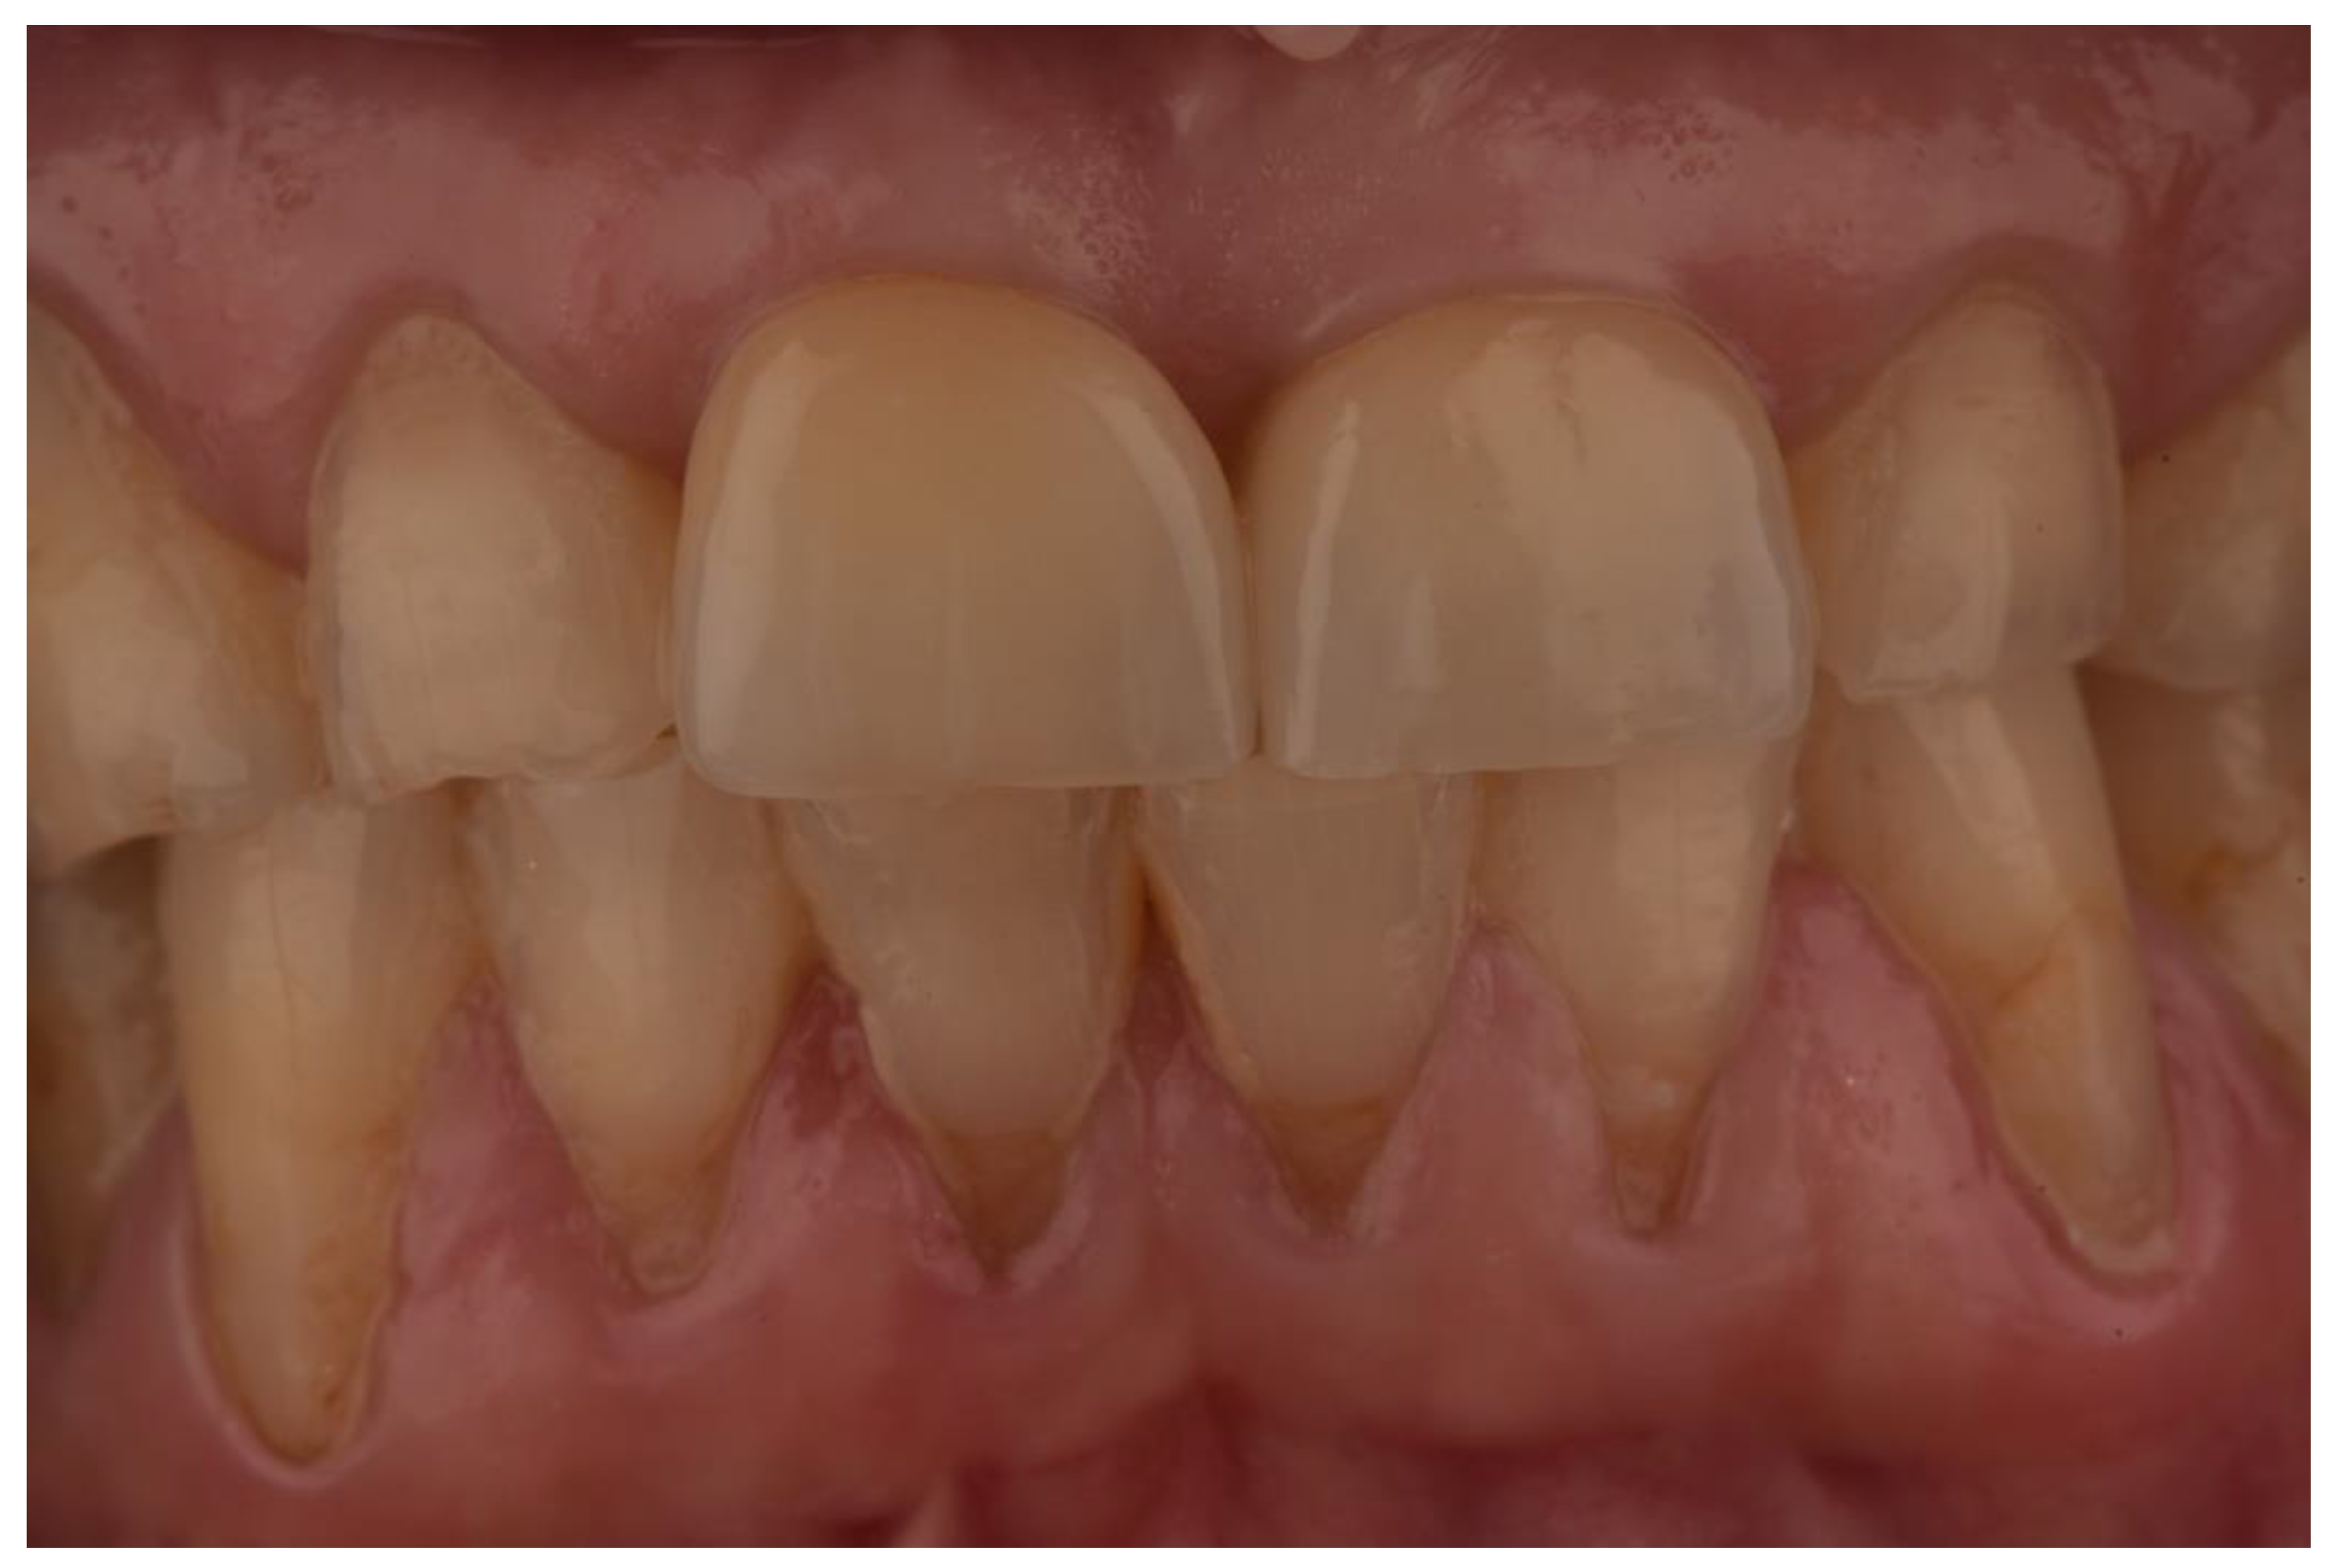

Single Crown Restorations Supported by One-Piece Zirconia Dental Implants: Case Series with a Mean Follow-Up of 58 Months

2. Materials and Methods

3. Results